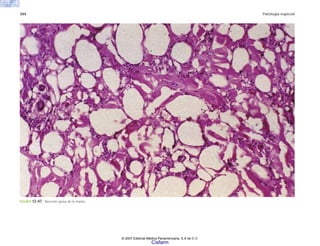

Glándula mamaria